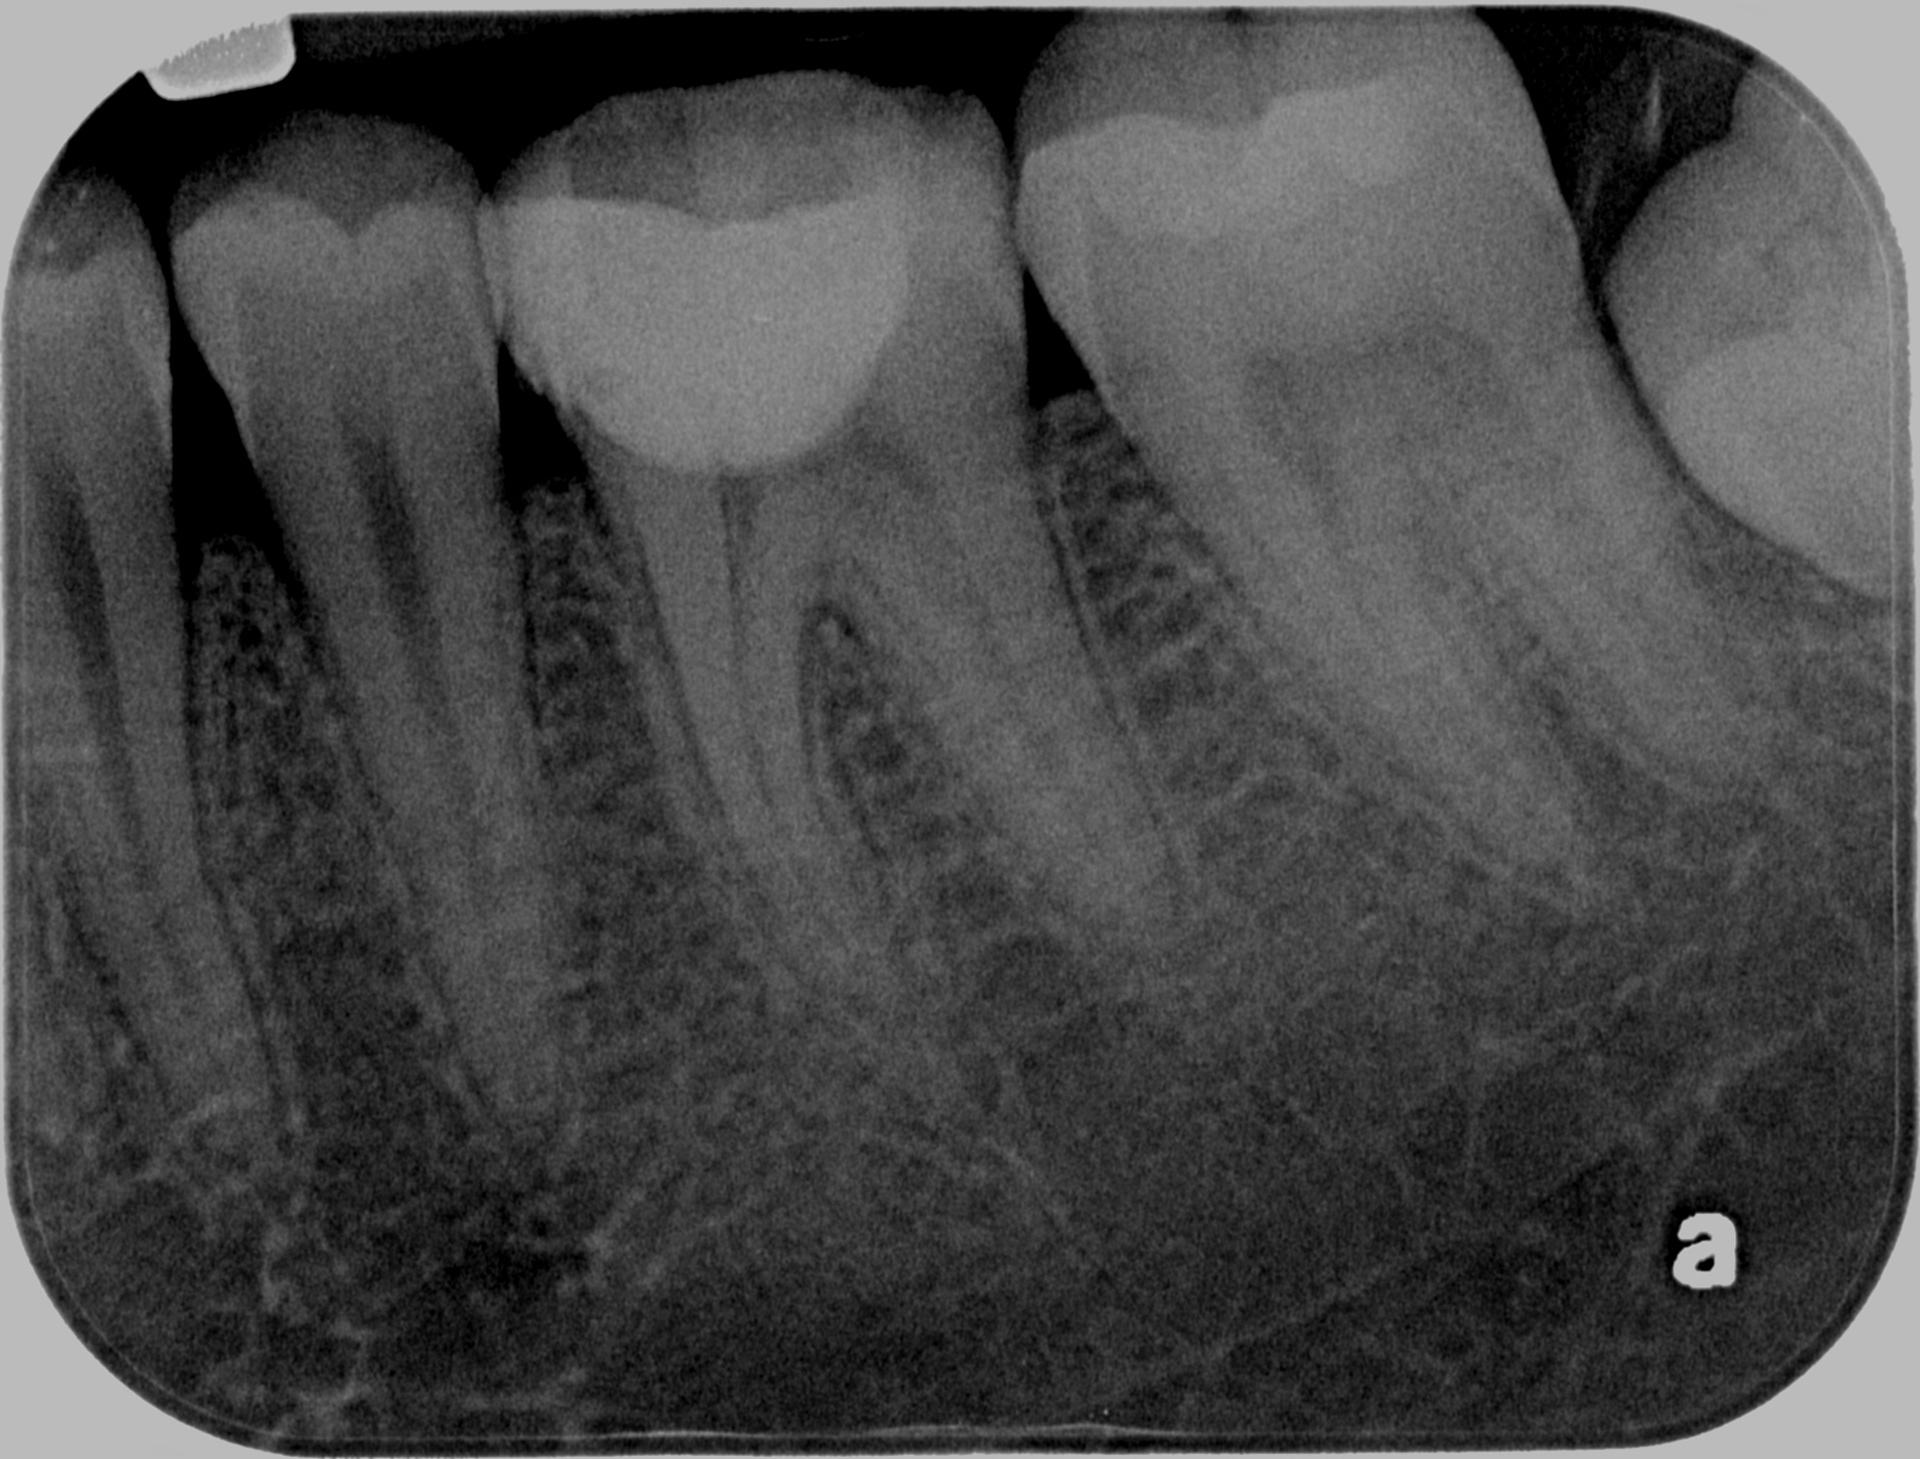

36 Selective caries removal - 3 month follow-up and Restoration

36 NTTP, Cold +ve, vital. 37 O caries

Initial